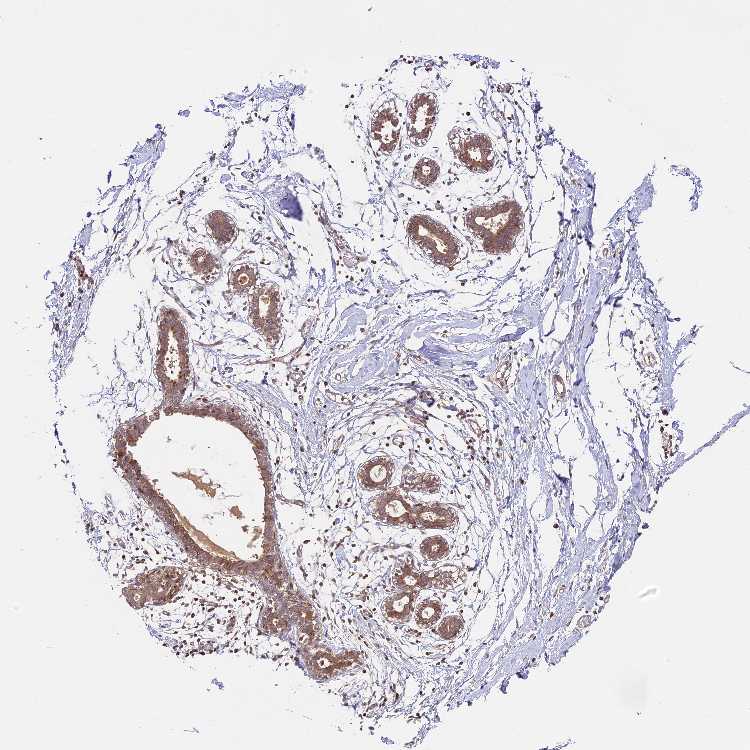

BREAST - Antibody stainingi

Antibody staining in the annotated cell types in the current human tissue is reported as not detected, low, medium, or high, based on conventional immunohistochemistry profiling in selected tissues. This score is based on the combination of the staining intensity and fraction of stained cells.

Each image is clickable and will lead to virtual microscopy that enables deeper exploration of all samples and also displays staining intensity scores, fraction scores and subcellular localization as well as patient and tissue information for each sample.

Antibody HPA039533Antibody HPA040355

Adipocytes Not detectedLow

Glandular cells LowMedium

Myoepithelial cells LowLow